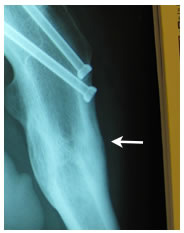

| Distal canal reamers encounter a bony bridge which was anticipated so intra-operative decision confirmed pre-operative plan to shorten the stem implant length. |

| Apex Modular Stem was used that features a special “Dual Press” modular junction. This design allows for selection of a variety of femoral offsets and one of three version angles: Neutral or 13º of anteversion or retroversion. |

| Pre-operative consideration was discussed on shorting the stem to avoid any potential femoral canal perforations. For this reason a special proximal modular stem “Dual-Press” design was utilized. Proximal conical reaming was done without the use of a pilot shaft along with rasping of the femoral triangle. |

Careful intra-operative measurements were done then surgery on the stem to customize “shortening of the stem” stem length. |

The Midas Rex® power system was used to cut the distal portion of the stem off.

| The stem fit was excellent with impressive implant to bone stability. The proximal modular neck design allowed selection of a variety of femoral offsets and neck lengths. This along with large head M-O-M (40mm) bearings provided significant ROM and hip joint stability. The short stem functions as a pilot with implant to bone stability provided by proximal stem geometry (cone & triangle). |